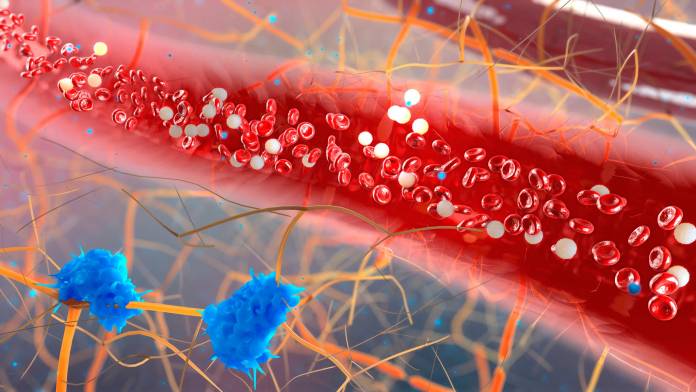

Weiße Blutkörperchen (Leukozyten)

Weiße Blutkörperchen sind für die Immunabwehr und die Abwehr von Krankheitserregern zuständig. Es gibt verschiedene Arten von weißen …